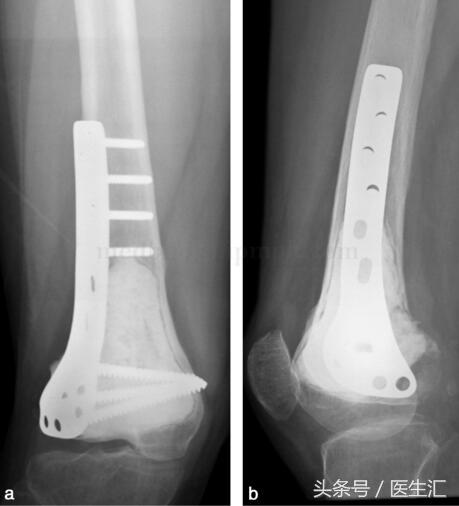

由于行軟骨下骨處植骨,故囑患者術(shù)后3個月,攝片示植骨愈合后,患肢開始負重(圖29‐4a,圖29‐4b)。此患者已術(shù)后隨訪兩年,局部無復發(fā),胸部無轉(zhuǎn)移,植骨已愈合,功能良好。

圖29‐4

a﹒術(shù)后X 線正位片;b﹒術(shù)后X 線側(cè)位片